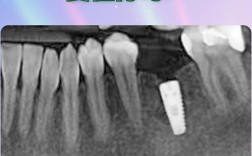

种牙前拍片是种植手术成功的关键前提,相当于为手术绘制“三维导航图”,通过影像学检查,医生能全面了解患者的口腔状况,包括牙槽骨的厚度、高度、密度,邻牙的健康情况,以及重要的神经、血管位置等,从而制定个性化的种植方案,避免术中损伤、种植体失败等...

种植牙作为目前修复缺失牙齿的理想方式,因其功能、美观接近天然牙,被越来越多缺牙患者选择,但在实际临床中,部分患者会被告知需要先“植骨”才能种牙,这让他们产生疑问:为什么种牙要植骨?这主要与口腔内的骨量条件密切相关,植骨是确保种植牙长期稳定使...